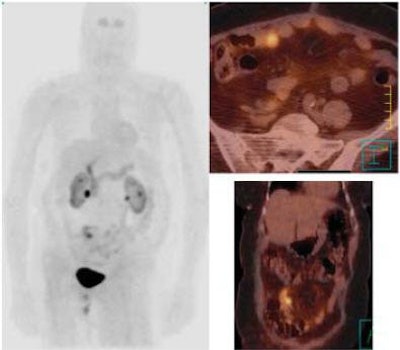

| A 52-year-old patient with pancreatic non-secretor neuroedocrine carcinoma low malignancy (NECLM; foregut; WHO type 2). SPECT and CT scans before start of 90Y DOTA TATE treatment, fusion images of standard CT after IV contrast enhancement and SRS using 99mTc HYNIC TATE. |

For this study, 19 patients with an established histological diagnosis of GEP-NET were treated with 90Y DOTA TATE. An objective response was measured using the response evaluation criteria in solid tumors (RECIST) guidelines (Journal of the National Cancer Institute, 2000 February 2, 2000, Vol. 92:3, pp. 205-216; European Journal of Cancer, May 2006, Vol. 42:8, pp. 1031-1019).

All patients received an average dose of 14.8 GBq in three to four therapy sessions over six to eight weeks. Anatomical response was assessed with CT as well as evaluation of clinical symptoms. Planar white blood cell scanning was used to confirm tumor uptake. Scans were judged based on partial response, complete response, disease stability, and disease progression using RECIST criteria.